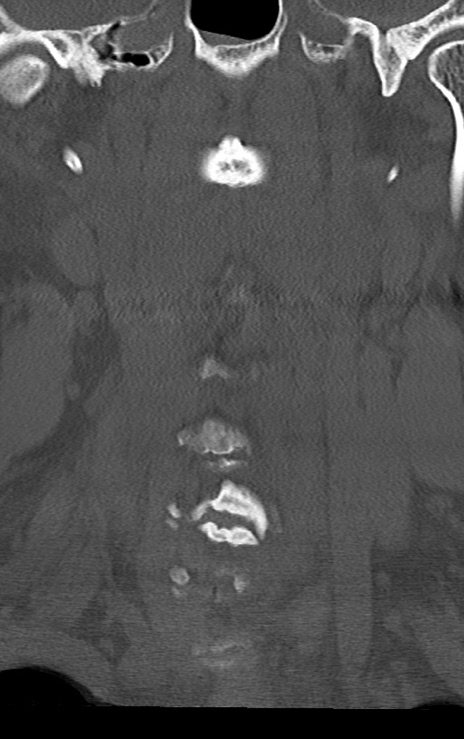

頚椎CT

矢状断像